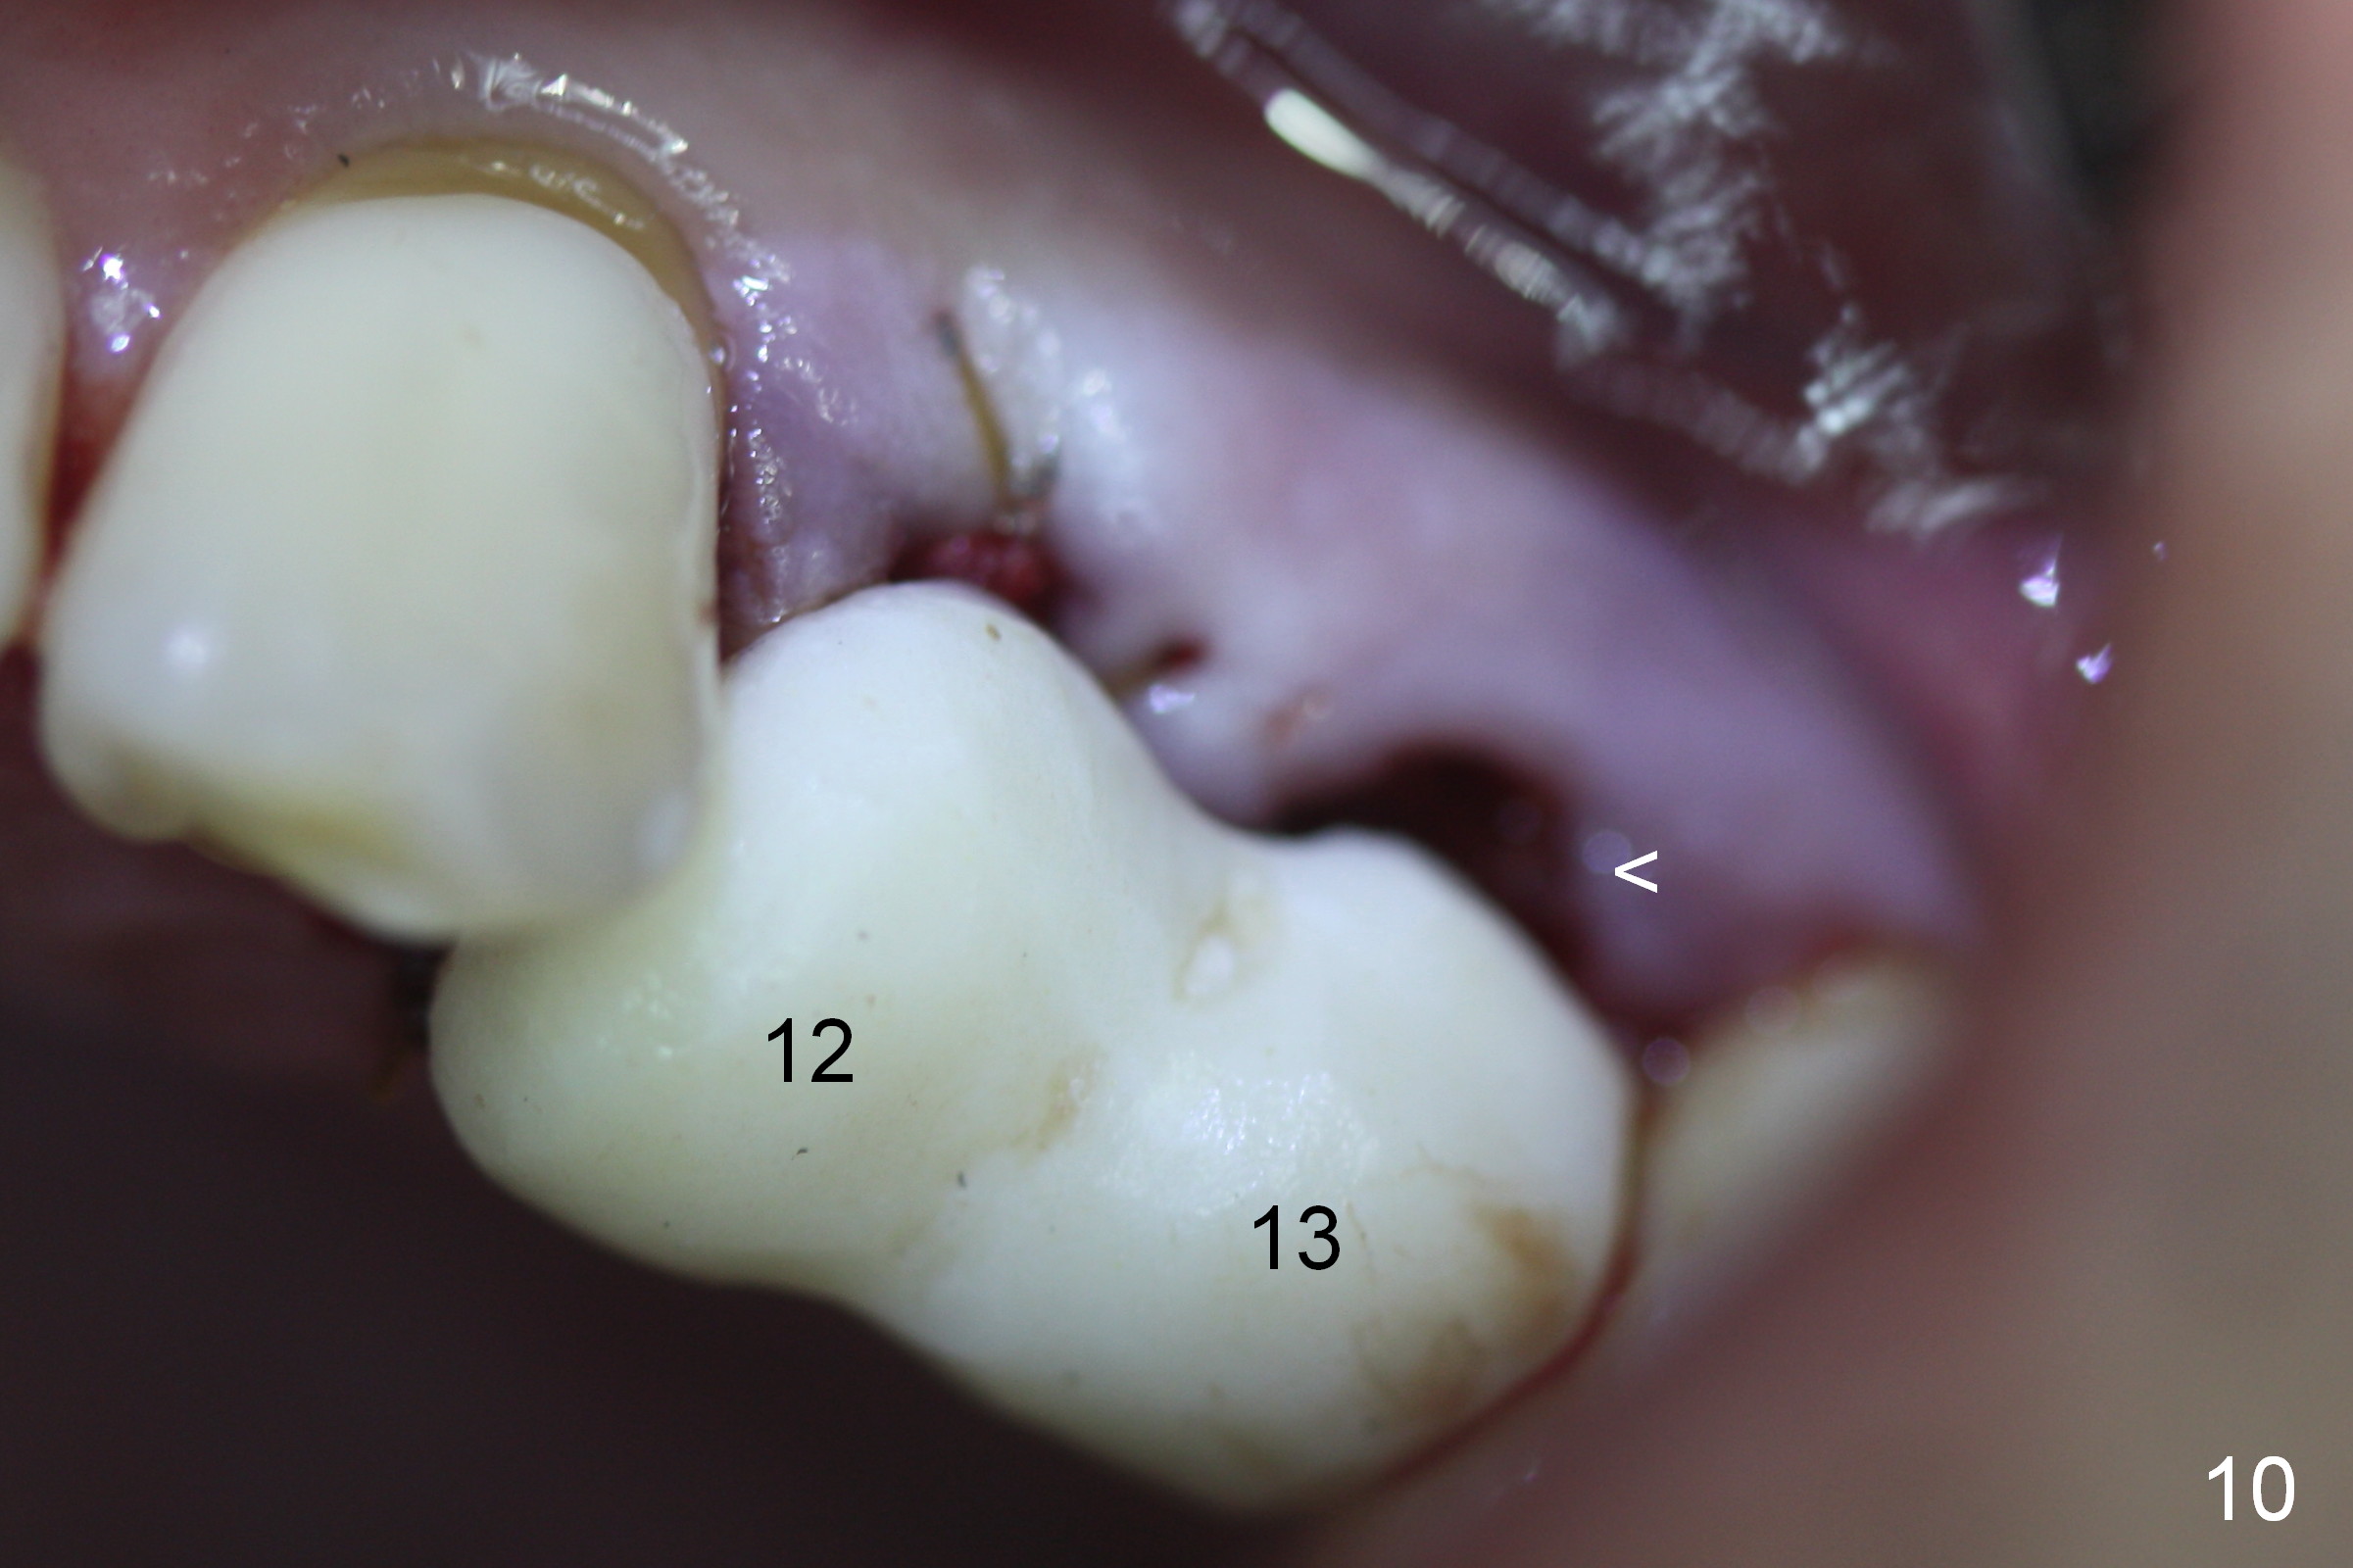

Taking 2 additional PAs with sensor 1 is frustrating (Fig.1,2), no apices shown. Osteotomy is done smoothly with 2 mm pilot drill at 20 mm, 2.5 mm reamer at 17 mm, and 3 mm reamer at 14 mm and 4.5x20 mm tap at 17 mm. The 1st intraop PA is taken with sensor 1 when 2 of 4.5x20 mm implants are placed (Fig.3); the implant at #12 is close to the root of the tooth #11. The 2nd PA is taken with sensor 2: the apex of #11 touches the implant at #12 (Fig.4). There is no separation when panoramic X-ray is taken (Fig.5). Effort is exerted to re-direct the osteotomy twice (Fig.6: tap; Fig.7: implant) without success. When the implant is removed, a PA is taken; it appears that the root of the tooth #11 has no damage (Fig.8). To obtain the best recovery, socket preservation is carried out with 50/50 cortical/cancellous allograft mixed with Osteogen (Fig.12 *) and Collagen Dressing (Fig.9: #12). A 2 (or 3)-unit provisional bridge (Fig.10: #12,13) is fabricated over the implant (Fig.9 I)/abutment (A) to cover these 2 sockets. After acid etching #11 D surface (Fig.9 >) and relining (Fig.11 *), the provisional bridge is bonded to the tooth #11 (Fig.11,12 black >) so that bone graft will be less likely dislodged.